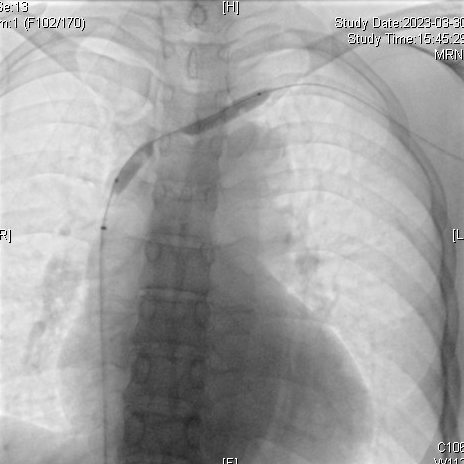

诊断:1、左头臂静脉闭塞,2、慢性肾衰竭尿毒症期,3、高血压。